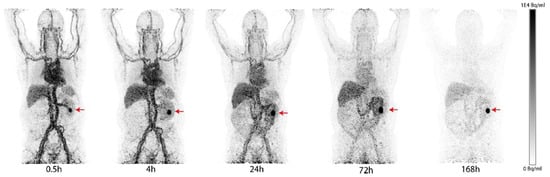

- Kulterer, O.C.; Pfaff, S.; Wadsak, W.; Garstka, N.; Remzi, M.; Vraka, C.; Nics, L.; Mitterhauser, M.; Bootz, F.; Cazzamalli, S.; et al. A Microdosing Study with (99m)Tc-PHC-102 for the SPECT/CT Imaging of Primary and Metastatic Lesions in Renal Cell Carcinoma Patients. J. Nucl. Med. 2021, 62, 360–365. [Google Scholar] [CrossRef]